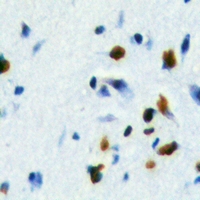

分类: 科研抗体货号: P43566别名: PCTK3; PCTAIRE; PCTAIRE3应用: IHC,IF反应种属: Human